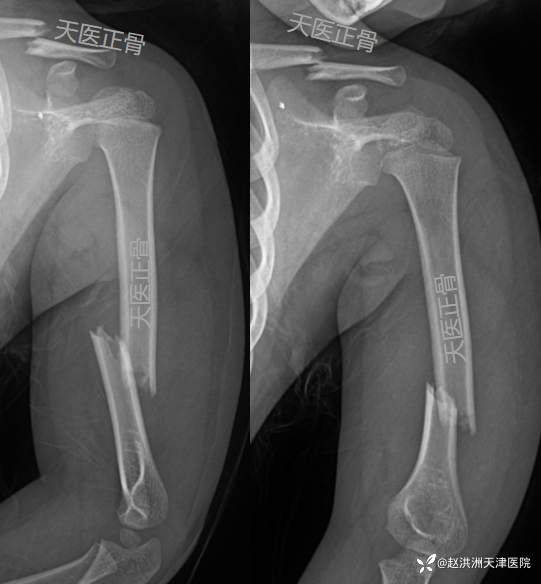

首诊X线片:左锁骨骨折+肱骨干骨折,重叠移位

复位后:肱骨对位可,残余轻度向外成角,锁骨重叠移位